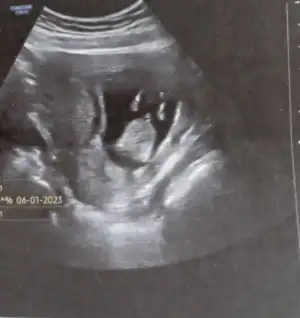

Biz öğrenemedik bir türlü dönmedi. Döndürmek için uğraşınca da poposunun üstüne oturdu Bi de el salladı bize. İnşallah salı günü öğrenicez. Hayırlı olsun oğlunuz. Sağlıkla gelsin.

Ay Allah'ım yerim yaa ben çikolata yedim girmeden zip zip zipliyodu ayırdı zaten direk bacaklarını fotoğrafını çekti hemen doktor da 😂 sağolun hepimizin ki sağlıkla gelir inşallah